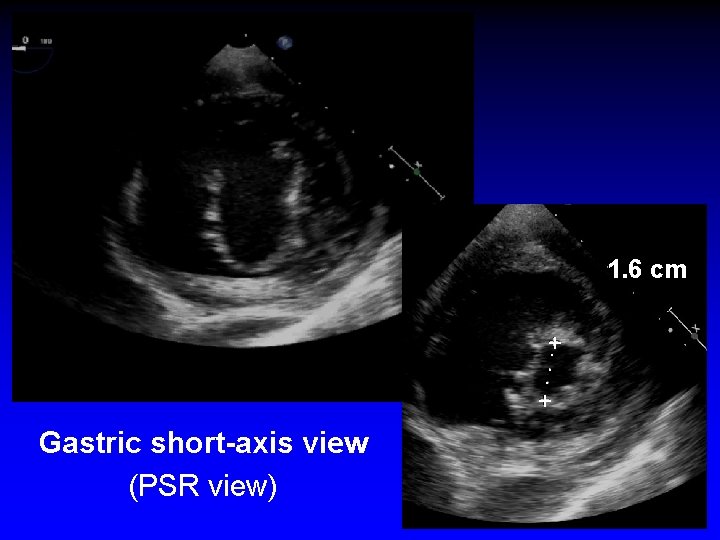

Case 1 Ruptured cords P 2

1. 6 cm +. . . + Gastric short-axis view (PSR view)